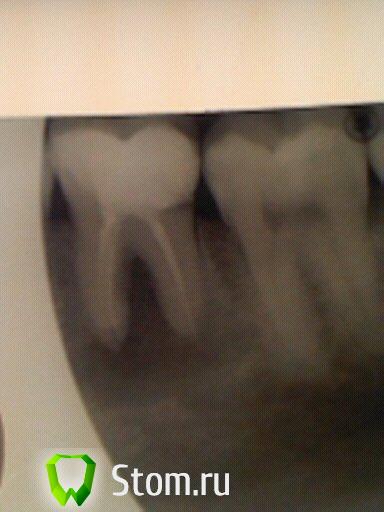

ARislanV Опубликовано 14 февраля, 2012 Поделиться Опубликовано 14 февраля, 2012 Можете,если не сложно,снимок Вашего фрукта вывесить?А вот и помелла))) 46з. Ссылка на комментарий

samsonov Опубликовано 14 февраля, 2012 Поделиться Опубликовано 14 февраля, 2012 А вот и помелла))) 46з.http://forum.stom.ru/topic/17755-nikakih-posplombirovochnih-bolei/page__st__20по -соседству тут созвучно немного....Есть ощущение в моих старых окулюсах ,что в медиальном корне металлический фрагмент.А так , 99%- зуб перелечится успешно надеюсь.В дистальном поискать второй...УДАЧИИиииии Ссылка на комментарий

ARislanV Опубликовано 16 февраля, 2012 Поделиться Опубликовано 16 февраля, 2012 (изменено) http://forum.stom.ru...ei/page__st__20по -соседству тут созвучно немного....Есть ощущение в моих старых окулюсах ,что в медиальном корне металлический фрагмент.А так , 99%- зуб перелечится успешно надеюсь.В дистальном поискать второй...УДАЧИИиииииКаналы прочистили, в дистальном нашли второй. Закачали метапекс, инструмента вроде не было. Доктор, а где тут у Вас протейперы? Я если честно не вижу нормального прохождения каналов до apex'a и кстати мыть после гипохлорида, хлоргексидином не очень вроде. Реакция между ними.Да, в медиальном похоже инструмент. Но лучше еще пару снимковПротейперы были, корни короткие 18 мм от жеватки, получилось то что получилось. Промывать хлоргексидином 0.1% !? - думаю уж лучше водой, хотя бы само обмана не будет. Под этими пломбами можно ещё кариес нарыть.Или эти пломбы глубоко под десну уходят.Поэтому лучше сначала всё старое убрать,не полениться и сделать преэндо.Так надёжней и на душе спокойней .Да + по тому что остается от тканей зуба, пациенту уже сразу можно сказать, что там будет пломба или коронка. Изменено 16 февраля, 2012 пользователем ARislanV Ссылка на комментарий

Heineken Опубликовано 16 февраля, 2012 Поделиться Опубликовано 16 февраля, 2012 Каналы прочистили, в дистальном нашли второй. Закачали метапекс, инструмента вроде не было.RE Мне кажется у Вас проблеме больше в медиальном. Попытался отметить на снимке, где вижу её. Ссылка на комментарий